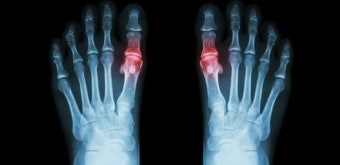

1. 통풍이란 무엇일까?

통풍은 단순히 발가락이 아픈 질환이 아니에요. 혈액 속 요산(지방이 아닌 노폐물)이 쌓여 결정 형태로 관절에 박히면서 생기는 염증 질환입니다.

요산 수치가 높아지면 통증이 반복되고, 결국 관절이 변형되거나 신장 기능이 떨어질 수 있어요. 통풍은 “시간이 지나면 낫겠지”가 통하지 않는 질환입니다.